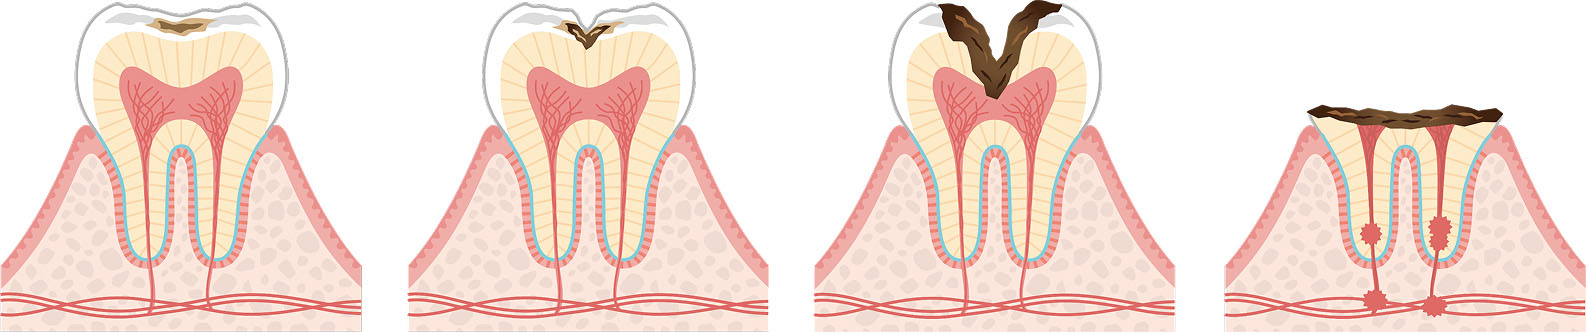

虫歯による痛み

進行した虫歯は神経を刺激し、痛みを引き起こします。初期~中期の虫歯は詰め物や被せ物による修復、神経に達した虫歯は根管治療、重度の虫歯は抜歯が必要な場合もあります。